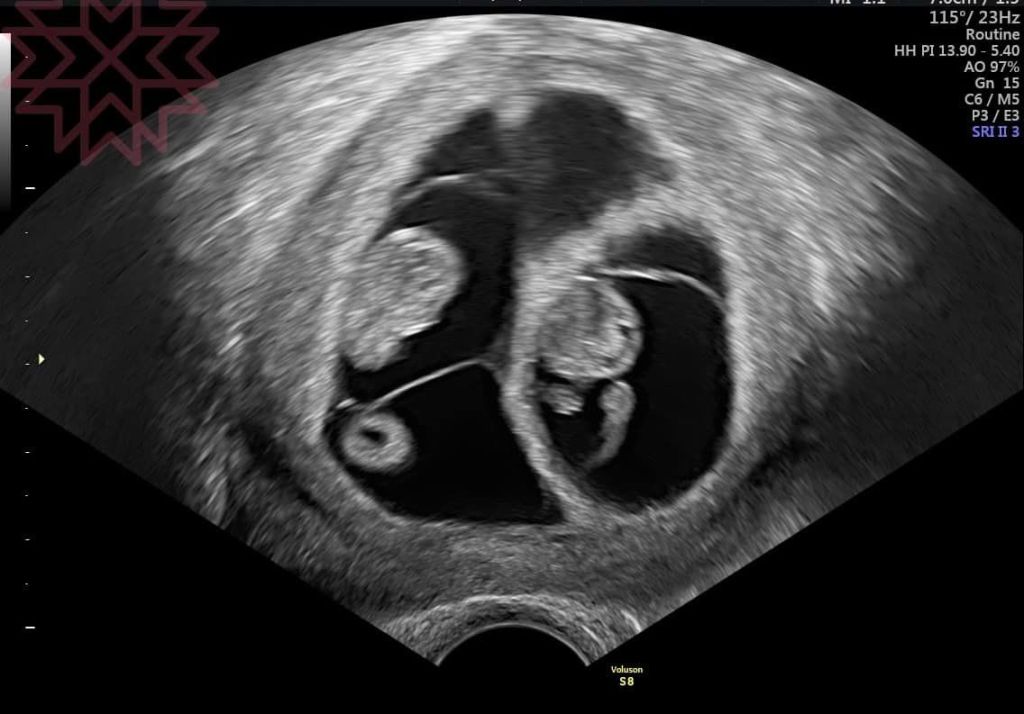

直接看圖

只要專業的醫師大概在這時候都可以知道哪一個是單絨毛膜雙羊膜哪一個是雙羊膜雙絨毛膜

3

單絨毛膜單羊膜(MCMA)雙胞胎

一定是同卵

兩個寶寶共用胎盤而且中間沒有羊膜隔間

這種雙胞胎風險是最高的

問題在於臍帶纏繞

胎死腹中的機率風險也是最高的

一定要及早發現並說明清楚並且擬定後續的策略

對了

隨便挑三張

抽考一下

大家看得出來這裡面分別有幾個羊膜幾個絨毛膜嗎?

答案之後公佈